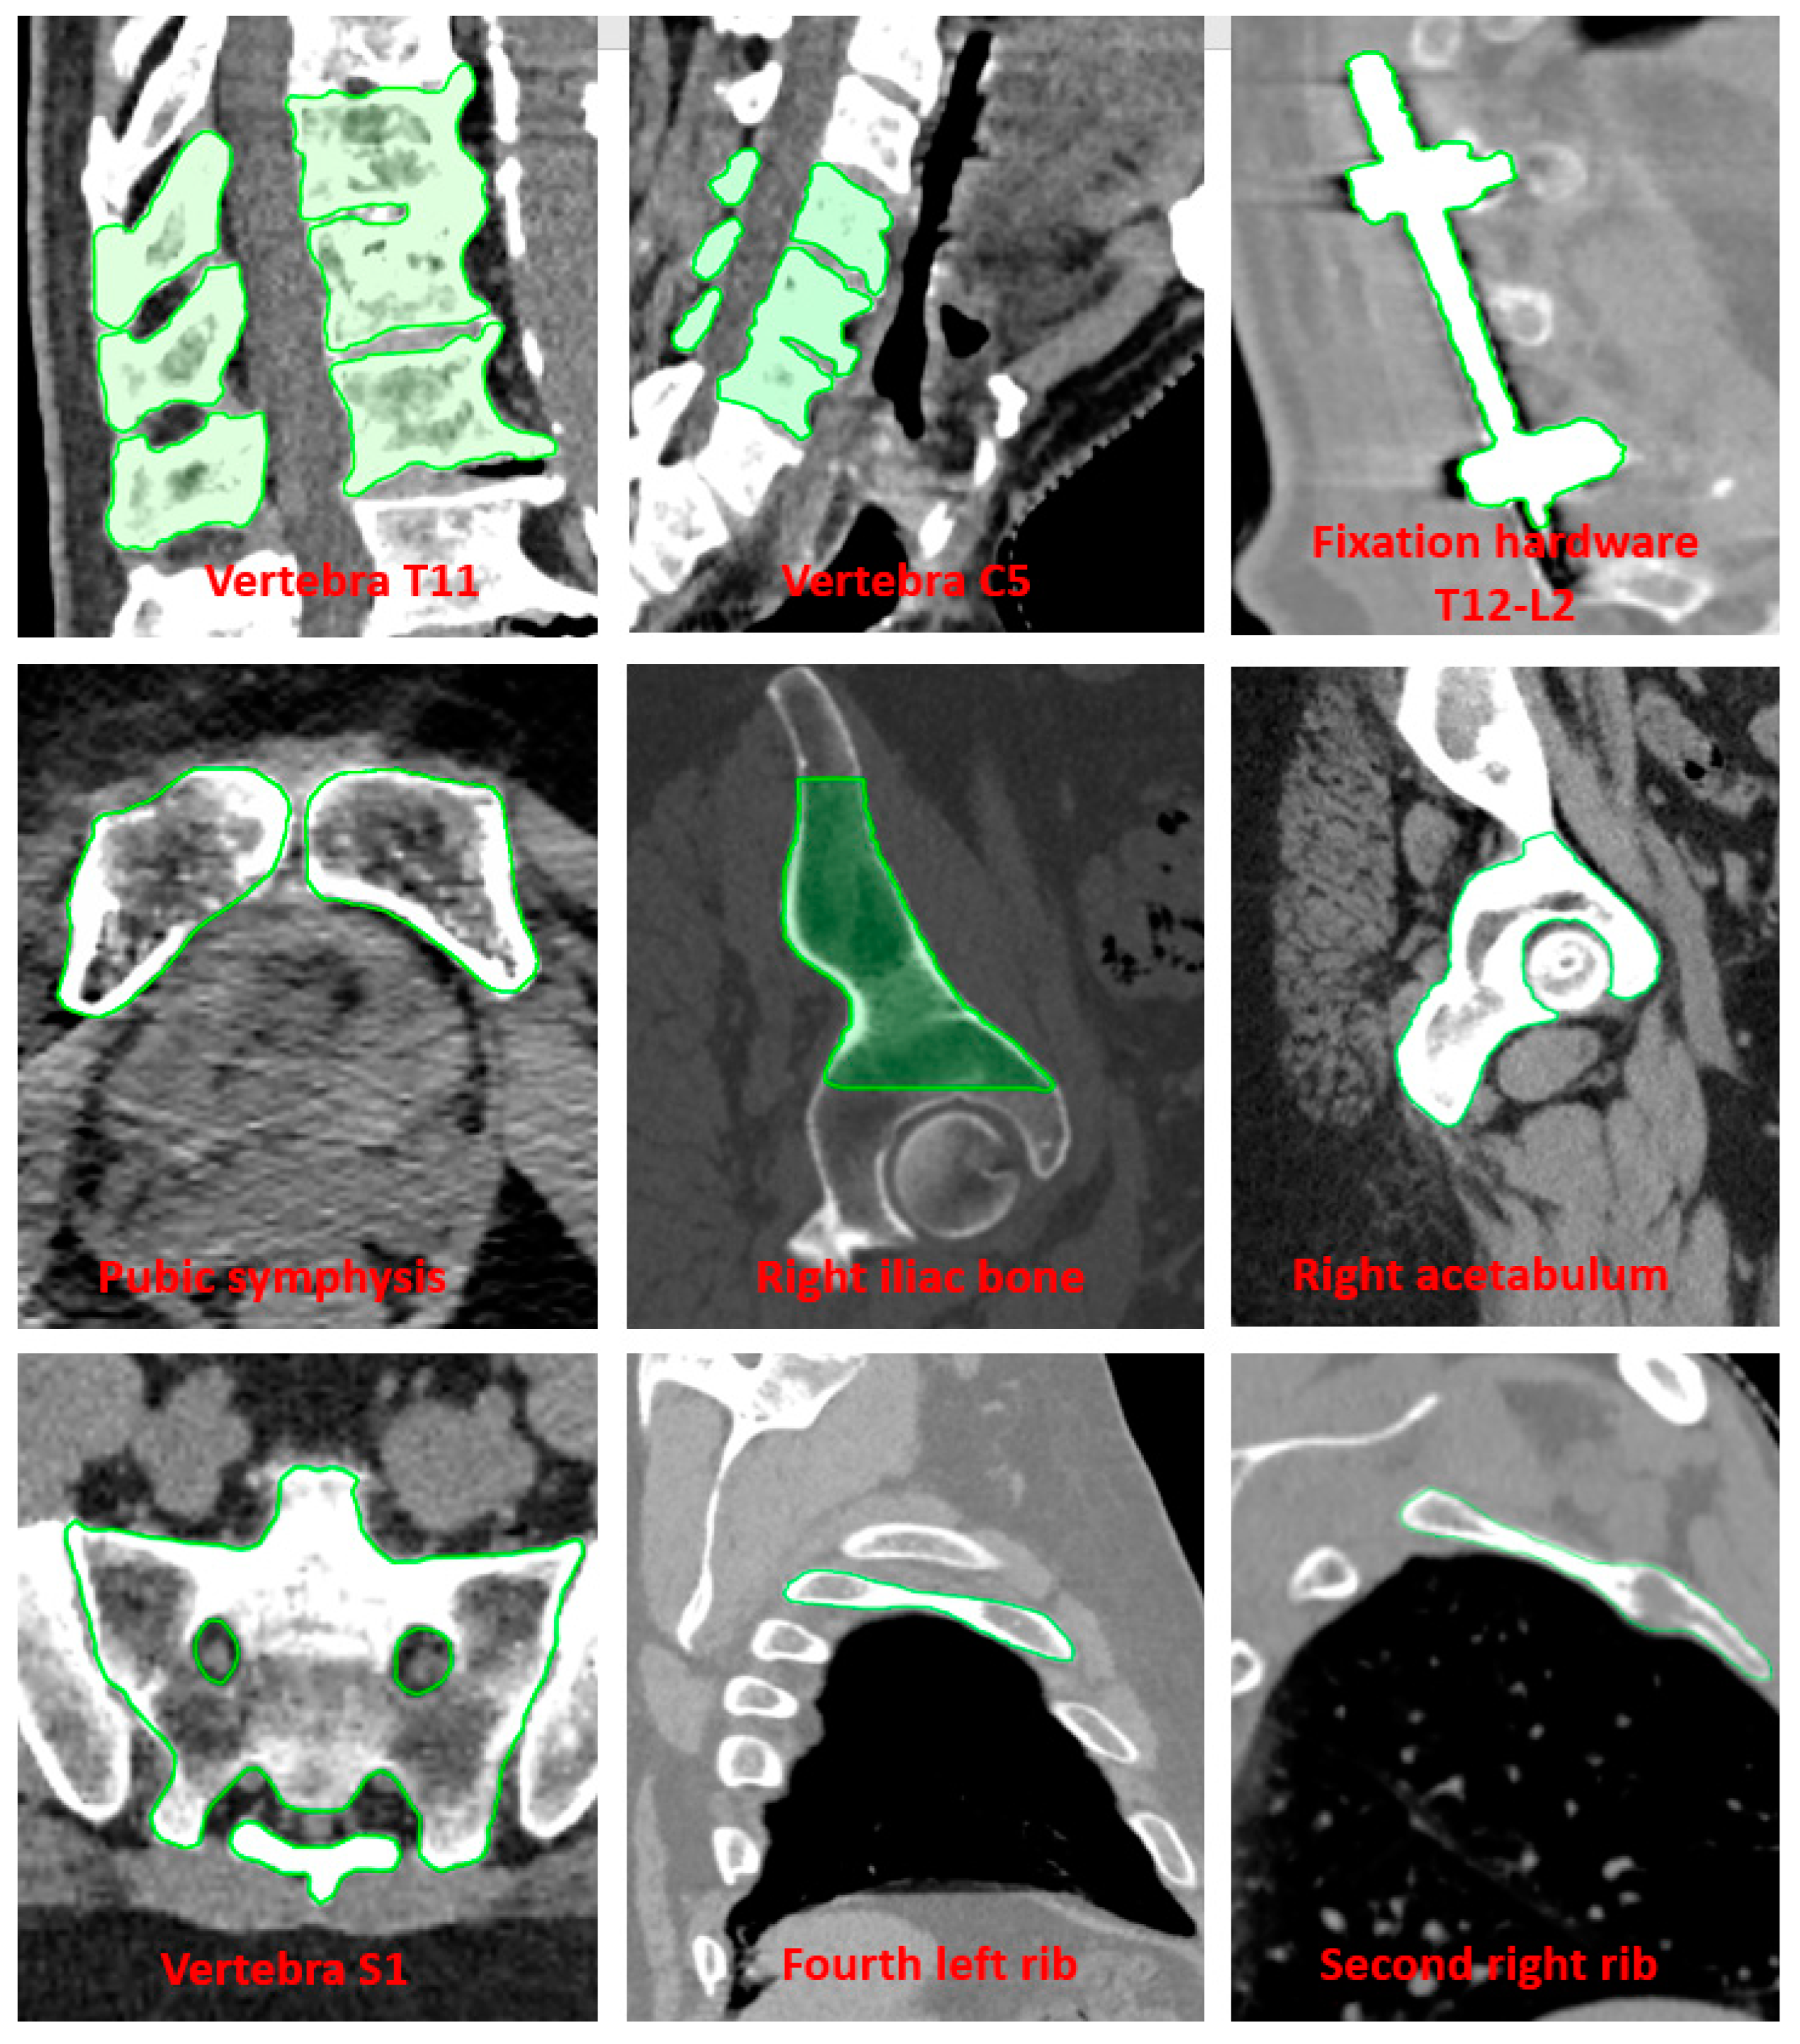

2.1. Phantom Study

2.3. Analysis Method

3.1. Phantom Study